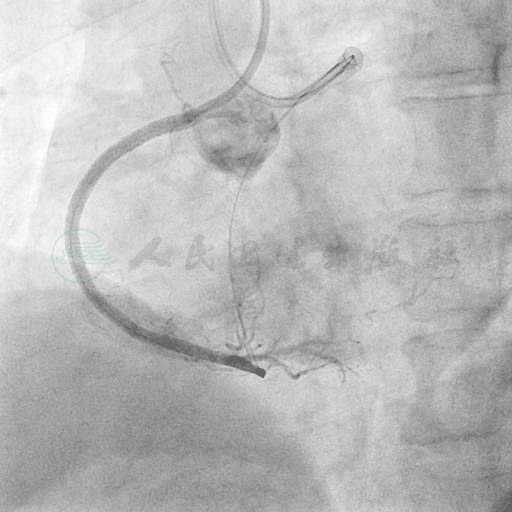

选用右侧桡动脉径路,6F血管鞘。造影发现:右冠状动脉(RCA)近端起完全闭塞,未见自身前向侧支循环供应远端(图5);左主干无严重狭窄,前降支近段至开口90%狭窄,回旋支中段70%狭窄(图6、图7);左冠侧支循环供应右冠远端(图8)。

图6 蜘蛛位造影提示左主干无严重狭窄,LCX中段70%狭窄

图7 头位造影提示LAD中段90%狭窄,左冠侧支循环供应RCA后降支,第3穿隔支似乎与后降支有直接连接(白色箭头所指)

图8 左冠LAO 45度造影可见侧支供应RCA远段及锐缘支,RCA中远段病变严重